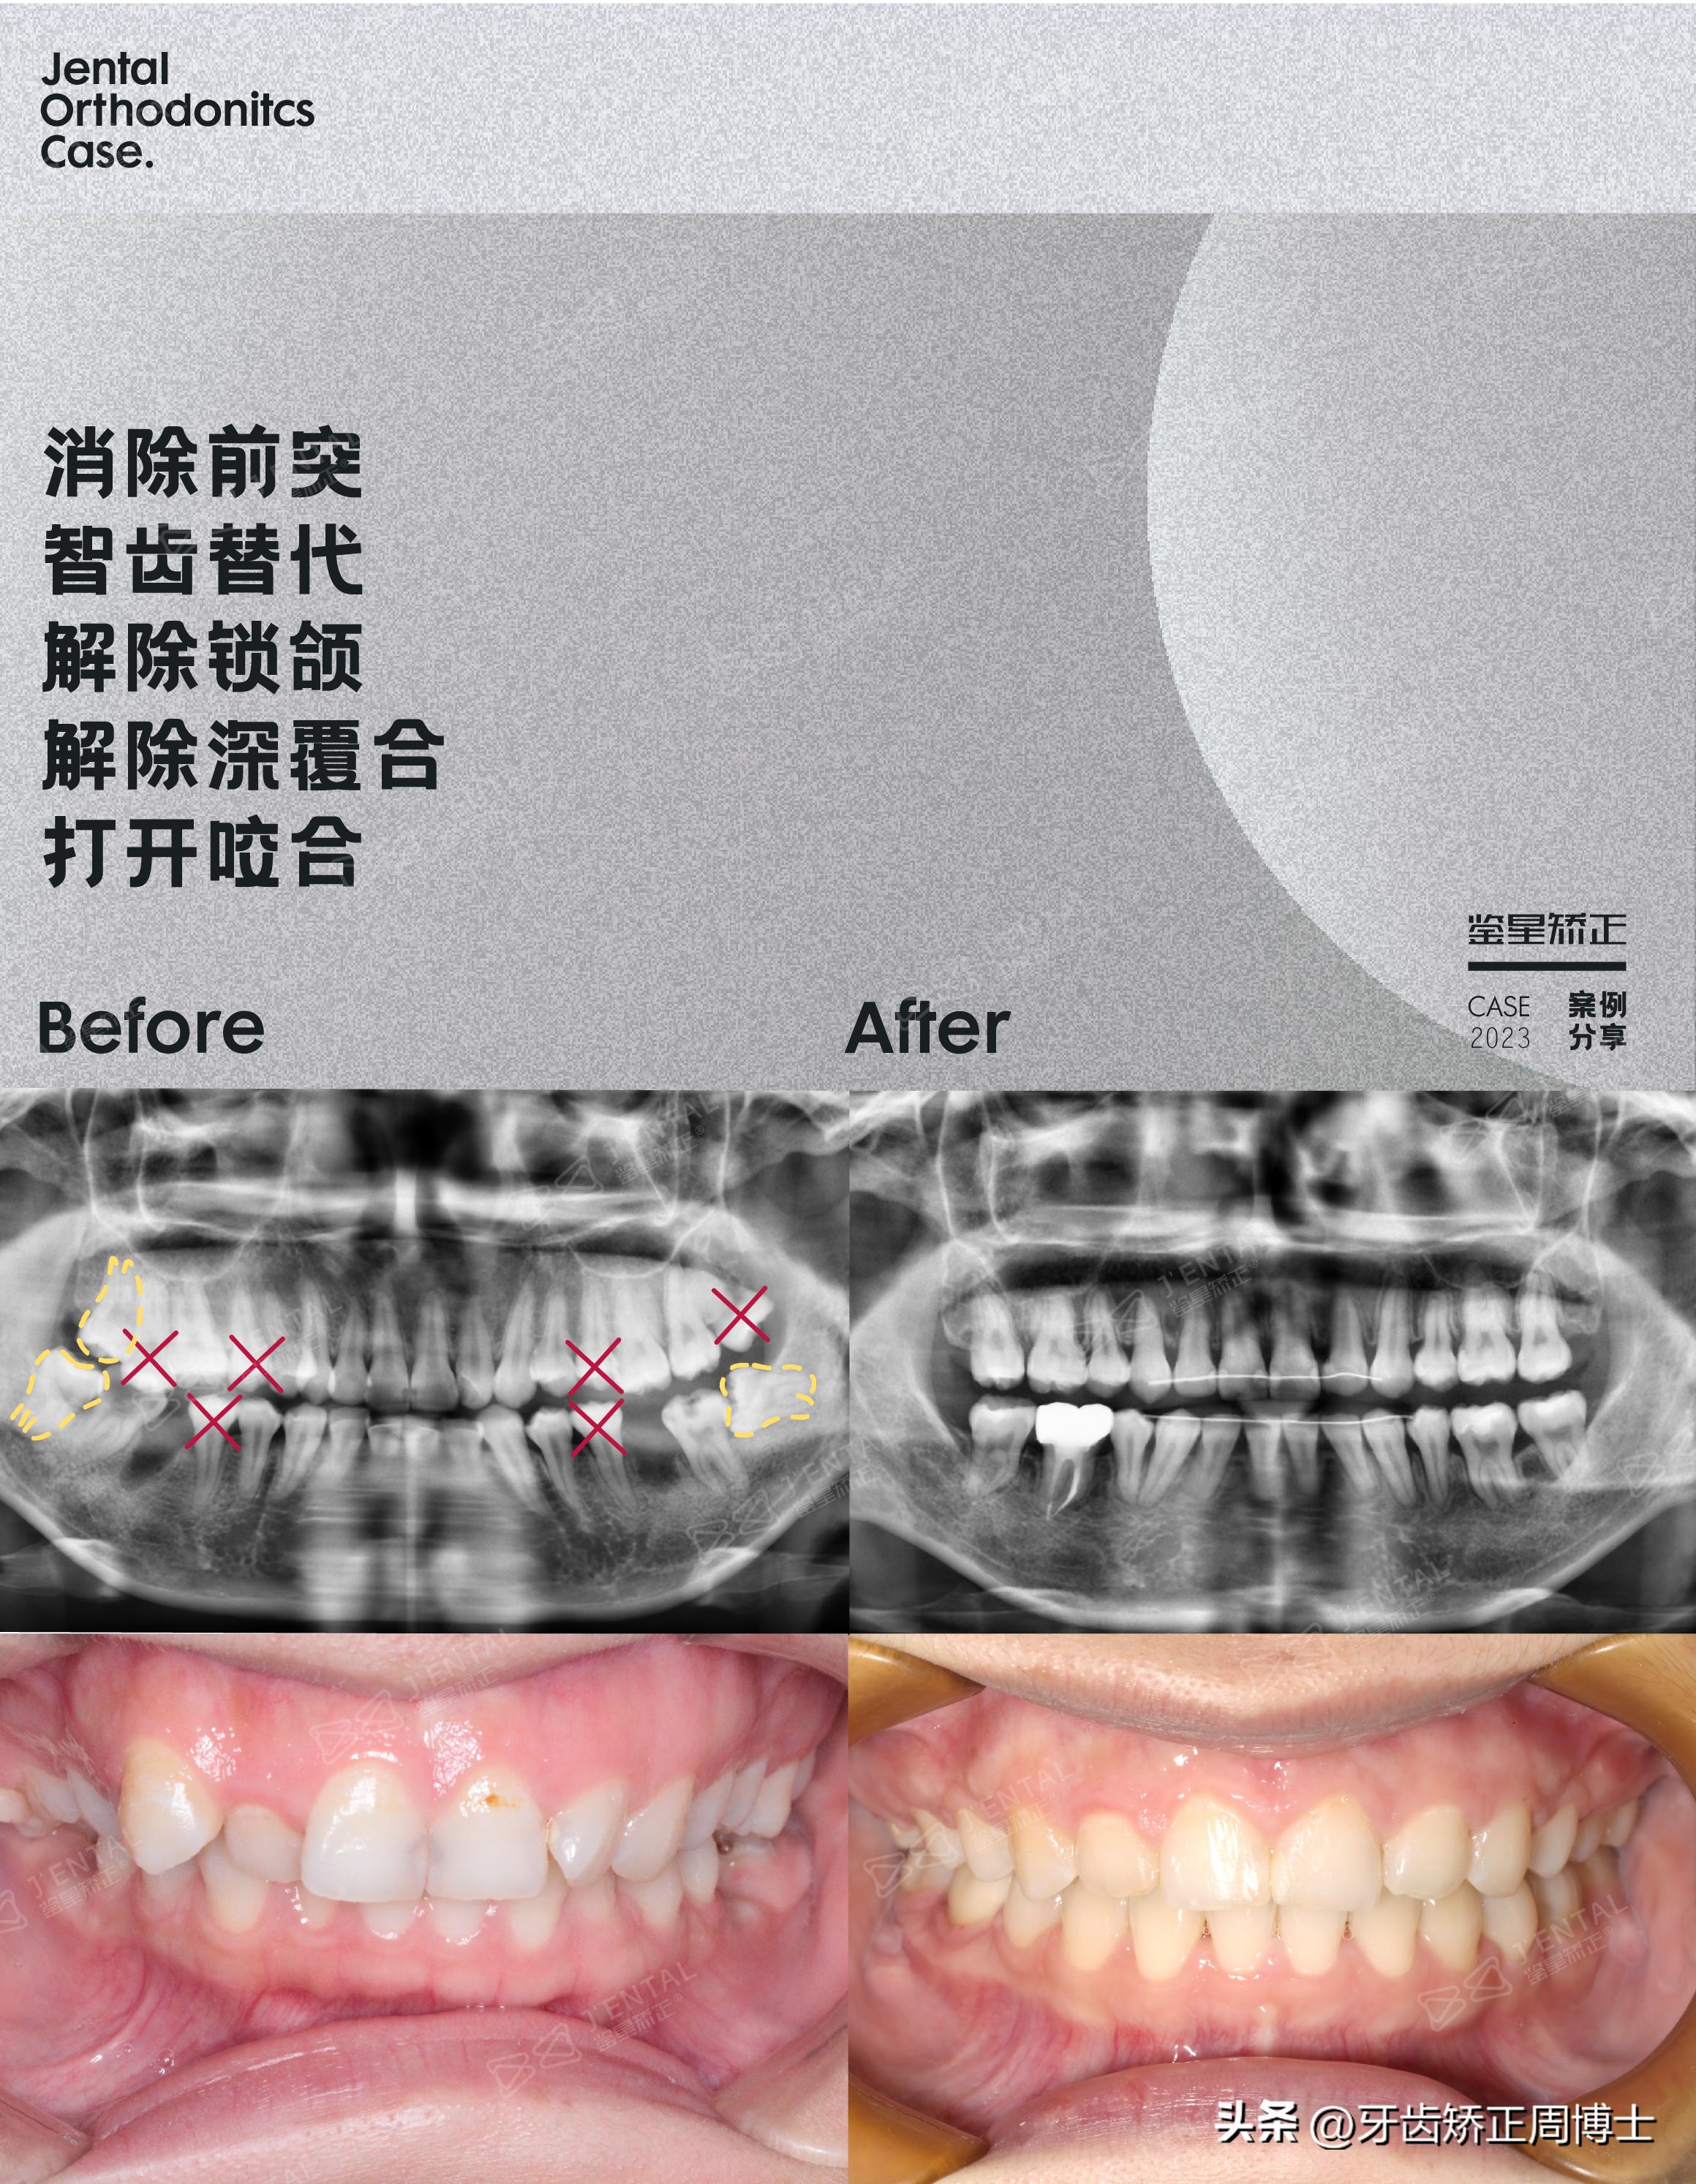

本期周医生为大家带来一个高角骨性前突下巴后缩➕重度拥挤➕大笑露牙龈➕后牙锁颌案例,方案设计三个象限智齿替代坏牙/缺牙,可以说是在混乱中创造秩序。

案例概况:高角骨性前突下巴后缩➕重度拥挤➕大笑露牙龈➕后牙锁颌

经过一番面诊检查,我们发现她的口内情况十分糟糕,做起来难度也很大。深覆合深覆盖,存在数十颗蛀牙,36.46缺失,17伸长,47根管后,17正锁颌,从x光可以看到发育过度的牙槽骨,这就是造成面型嘴突下巴后缩的原因!

针对这些情况,我们进行了拔牙方案,拔除15.17.25.28,拍ct确认37.47是否存在保留价值,若能,则在术中追加拔除35.45,若不能,则对35.45进行术后冠加大处理。

此外还在三个象限处进行了智齿替代的操作,38扶正牵引,48牵引,38.48代37.47,18牵引,18代17,再通过8-9颗骨钉进行垂直向控制,既免除了种植牙的麻烦,又帮助她改善咬合与面型。